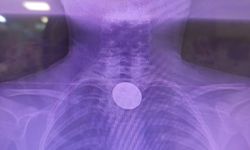

Rahim ağzı kanserine yönelik taramalara dikkat çeken Küçükşen, “Özellikle rahim ağzı kanserine sebep olan ve halk arasında ‘mikrop’ olarak bilinen etkenin taramasını yapıyoruz. Bu etken yaklaşık 10–15 yıl içerisinde kansere dönüşebilen bir sürece sahiptir.” dedi.

Erken teşhisin önemini vurgulayan Küçükşen, “Biz bu durumu erken evrede tespit ettiğimizde, henüz kanserleşme sürecine girmeden etkin tedavi yöntemlerimizle bu süreci geri çevirme şansımız olabiliyor.” diye konuştu.

Meme kanseri taramalarına da değinen Küçükşen, “Meme kanseri taramalarında da erken evrede teşhis konulduğunda, bazen küçük bir cerrahi müdahale ile bile tedavi şansı oldukça yüksek olmaktadır.” ifadelerini kullandı.